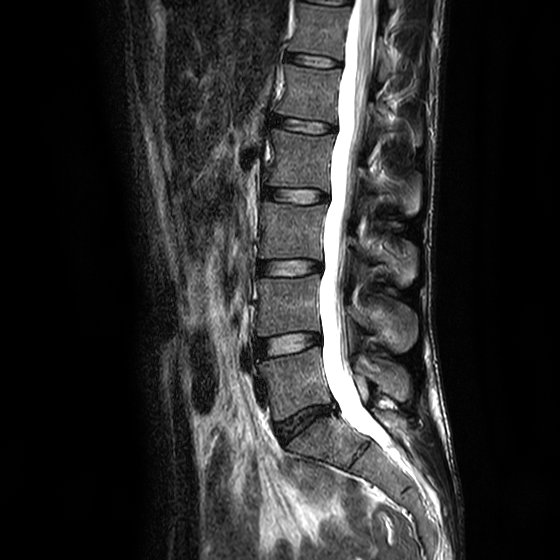

Hab mal 2 Bilder ausgesucht....einmal die Bandscheibe L5/S1. Da sieht man schon das der Kern beschädigt und nicht mehr intakt ist und das Gewebe Richtung Spinalkanal austritt. In dem Bild geht es noch. In anderen Aufnahmen ist es noch deutlicher zu sehen. Ich finde aber auch dass das alles etwas täuscht im liegenden und entspannten Zustand. Und dann das Becken bzw. an den Gelenken finde ich sieht man ganz gut den Unterschied.

H071D9FB00.jpg

H071D9FB00.jpg (20.41 KiB) 26163 mal betrachtet

H071DA0A00.jpg

H071DA0A00.jpg (46.7 KiB) 26163 mal betrachtet

Zumindestens in der LWS sehe ich bei Dir höchstens eine minimale Skoliose, die wahrscheinlich nicht behandlungsbedürftig ist. Definitiv kann Dir das nur ein auf Skoliose spezialisierter Arzt sagen. Bei Dir geht es bestimmt nicht um eine Skoliose-OP sondern "nur" um die durch den LWS Verschleiss hervorgerufene Probleme. Ein Skoliose-Korsett wirst Du bestimmt nicht brauchen. Wenn Korsett dann wird das ein reines Stützkorsett und das ist viel besser zu tragen. An Deiner Stelle würde ich bei den Ärzten eine minimalinvasive Therapie durchsetzen mit PRT-Spritzen an die schmerzenden Wirbel als Anfang.